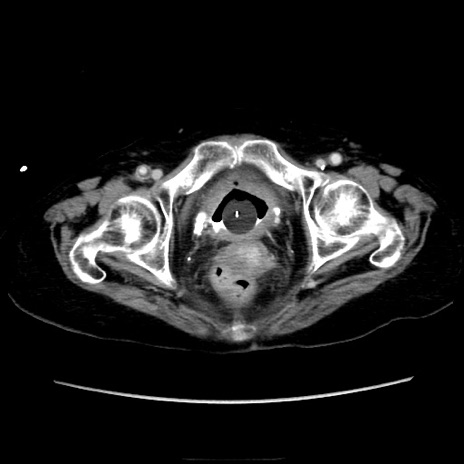

症例40(横断像)

【症例】90歳代女性

【主訴】腹痛・嘔吐

【現病歴】 食欲低下、嘔吐があり昨日他院受診。肺炎と診断され入院となる。入院後より腹部全体に圧痛あり。胃管留置され経過みていたが、症状持続するため、

当院転院となる。

【既往歴】胸椎圧迫骨折、胆石症

【身体所見】腹部:中央に激痛あり、圧痛あり、反跳痛不明

【データ】WBC 17100、CRP 18.82

横断像